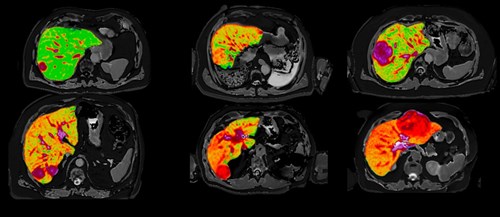

The ELEGANCE study’s objective is to recruit 2000 participants who are under surveillance for developing HCC in Singapore. Participants will receive blood, urine, stool and genetics tests, ultrasound imaging as well as Perspectum’s advanced non-invasive multiparametric MRI technology, LiverMultiScan® (see Figure 1). LiverMultiScan will be used to quantitatively assess liver tissue health, providing measures of liver fibro-inflammation and fat, which are key indicators of liver disease [3]. These measures have been shown to correlate with liver biopsy and to predict clinical outcomes in patients with chronic liver disease [3-5].

Figure 1: Quantitative MR images of the liver from six patients with liver cancer, produced by Perspectum’s LiverMultiScan. Published in Mole DJ et al. Plos One. 2020;15(12):e0238568.